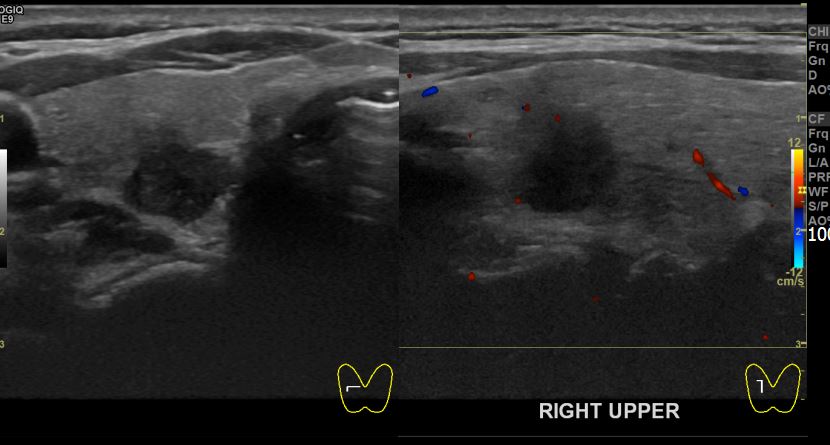

상기환자 건강검진상 이상소견으로 내원하신 50대중반 여성분으로 우엽 의심스러운혹

세포검사진행후 갑상선암으로 진단되었습니다